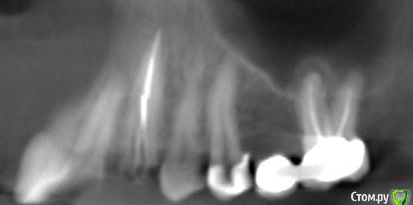

platerx Опубликовано 21 декабря, 2015 Поделиться Опубликовано 21 декабря, 2015 (изменено) Всем доброго времени суток.У меня есть пара вопросов: 1. Что можно сделать с зубом 2.7 История зуба такова:Зуб был сильно разрушен, но мне предложили попробовать пролечить его. Прочистили каналы, я некоторое время ходил с лекарством в зубе. Затем запломбировали каналы и поставили вкладку и коронку (консоль). Это было 2,5 года назад.С тех пор зуб меня иногда немного беспокоил, вызывая некоторый дискомфорт, но я не сильно обращал внимание. В последнее время он стал беспокоить сильнее: время от времени вызывает тянущие и распирающие ощущения, которые усиливаются при нажатии. Слегка побаливает десна и небо с внутренней стороны. Периодически ощущения пропадают. Прикладываю срезы КТ этого зуба. Что можно сделать с этим зубом ? Можно ли извлечь вкладку и перелечить каналы ? 2. При депульпировании зуба 2.4 врач не промывал каналы гипохлоритом (только хлоргексидином), после чего запломбировал их. Это нормально или стоит переделать? На зубе сейчас временная пломба, по прошествии 6 дней зуб не беспокоит. При постукивании есть небольшие неприятные ощущения. Изменено 21 декабря, 2015 пользователем platerx Ссылка на комментарий

DmitrySH Опубликовано 21 декабря, 2015 Поделиться Опубликовано 21 декабря, 2015 Добрый вечер.27. Есть очаг воспаления на одном из корней. Нужно снять коронку, оценить объём тканей. Если все ок, то извлечение вкладки и ревизия каналов.24. Сложно дать однозначный ответ. После выяснения ситуации с 27 планировать имплантацию в области 26 или 26, 27 (если с 27 все плохо) Ссылка на комментарий

St. Опубликовано 21 декабря, 2015 Поделиться Опубликовано 21 декабря, 2015 (изменено) Консоль не есть хорошо, тем боле на жевательных зубах. Это приводит к перегрузке.Кмк, на будущее стоит задуматься о смене конструкции в этой области. Изменено 21 декабря, 2015 пользователем St. Ссылка на комментарий